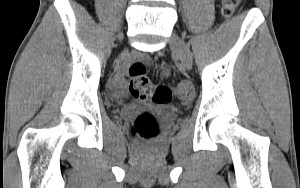

Мужской малый таз

Женский малый таз

Тазобедренные суставы